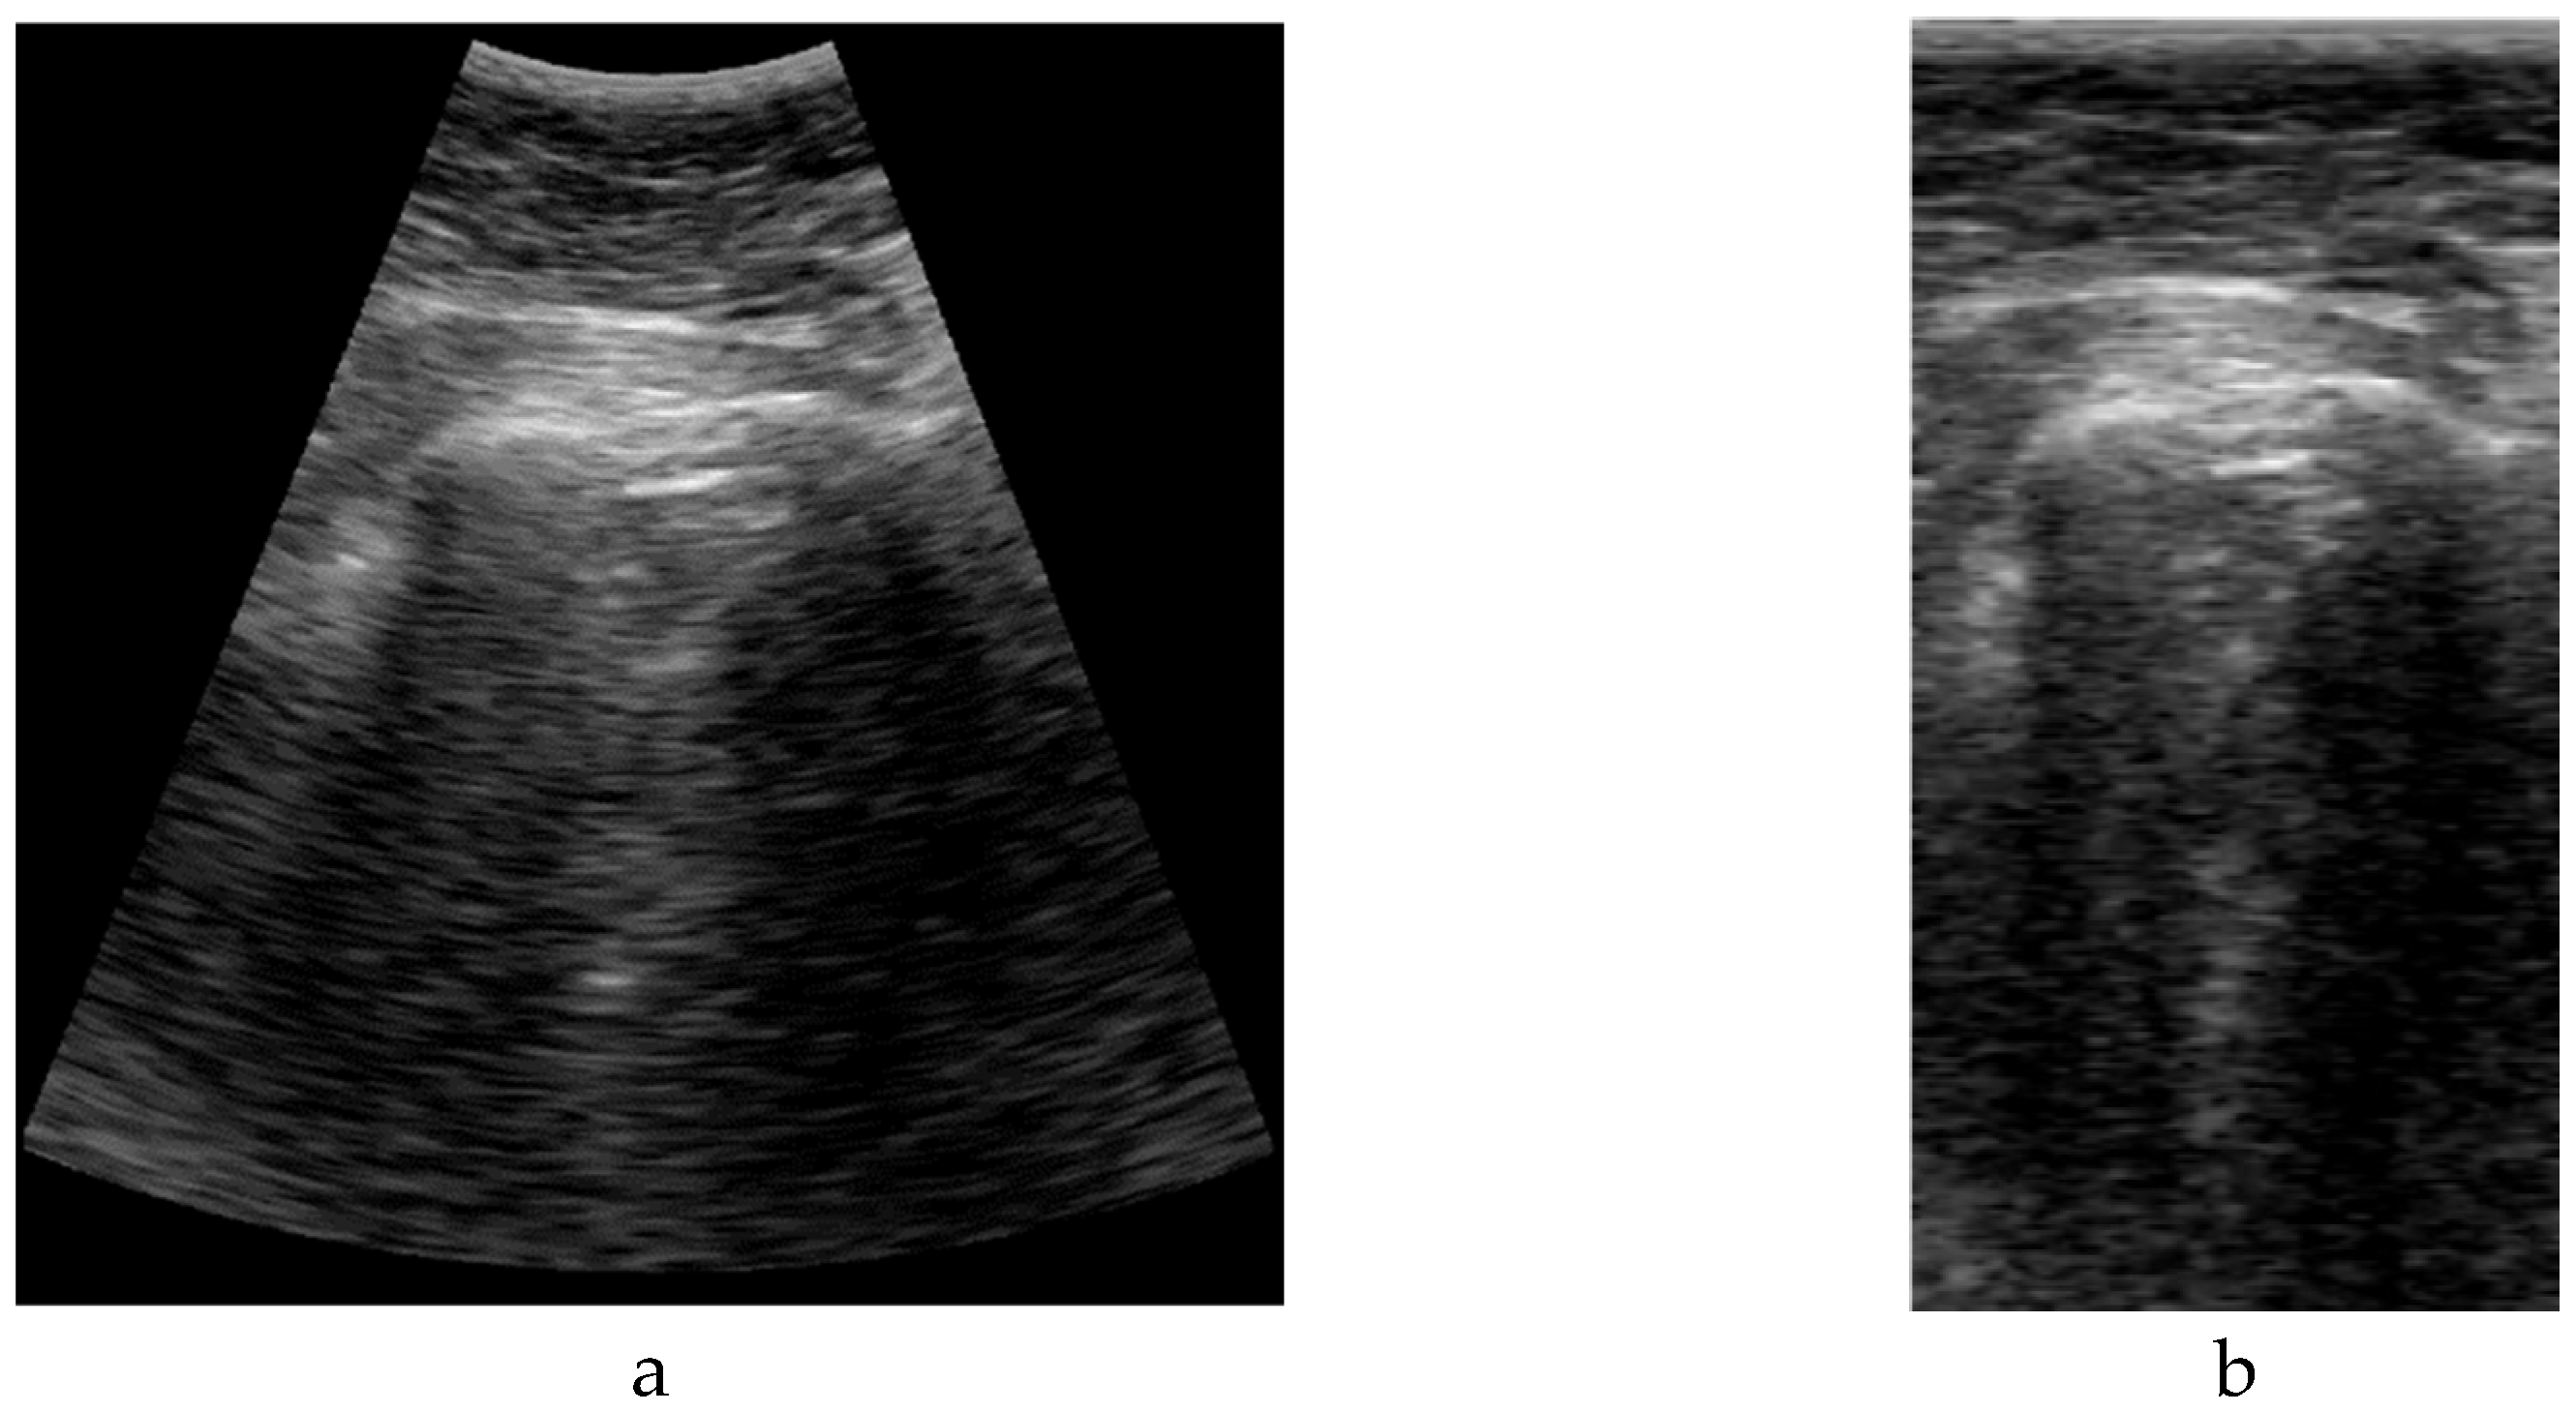

The format of the input data has a great impact on the deep learning model definition and performance. A typical ultrasound image with a curved array (like that used in this study) is a circle sector, defined by an aperture angle α, an initial range r1 and a final range r2, which is usually framed into a rectangular image with size WxH pixels (Figure 2.Left). But, in fact, a sector ultrasound image is originally formed by N scan lines usually equal distributed inside the sector area. These lines, containing M samples each, are the output of the beamforming algorithm, and could be interpreted themselves as a rectangular image (Figure 2.Right).

The algorithm to get the sector image from the B-Scan data is usually called scan-converter, and it is typically implemented by bi-linear interpolation of the acquired samples over the pixel grid. This process is carried out by the scanner, which gives the user the sector image in WxH format. Therefore, a question arises about which image format is more appropriate for implementing the deep learning algorithm aimed in this work.

Sector image has the advantage of being more easily accessible, because it is the typical output format on most ultrasound equipment. Therefore, it maintains the aspect ratio of the structures to be imaged, which eases interpretation by medical professionals. However, accommodating a sector image inside a rectangular grid generates black margins around it, which besides adding pixels with no information, could potentially introduce a bias in the automated image analysis. Furthermore, the shape and extension of these zones depends on the scanner model and configuration, hindering the translation of the resultant model between different scanners.

On the other hand, rectangular B-scan images have the advantage of providing only useful information (no black margins), while its rectangular format is highly suitable as input for segmentation models. Another important advantage is that each vertical line represents a physical propagation direction of the beam inside the tissue, which is particularly relevant for artifacts like B-Lines, that appears precisely on those directions. Therefore, a B-Line will be always seen in the B-Scan as a vertical artifact, independently on its position on the pleura, and of the scanner configuration. Furthermore, scanner configuration parameters like the aperture angle α or the initial and final range r1 and r2 only affect the size MxN of the image, which simplifies adapting images acquired by different equipment to the same network, only by vertical and horizontal scaling. On the other hand, these images are not suitable for visual interpretation, as they present a distorted view of the tissue anatomy. Because not all ultrasound equipment provides direct access to B-Scan data, a Sector-Image-to-B-Scan conversion algorithm would be needed. With a similar approach than scan-converter algorithms from B-Scan to sector image, it could be based on a simple bilinear interpolation algorithm, after defining a set of beam lines that cover the useful area of the sector image (green lines in Figure 2.Left). In this work, we had access to the B-Scan raw data generated by our system, so no Sector-Image-to-B-Scan process was needed.

Figure 3. Comparison between sectorial image (a) and B-Scan (b).